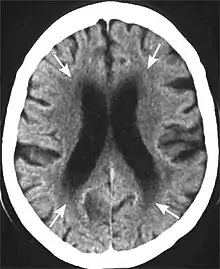

Leukoaraiosis is a particular abnormal change in appearance of white matter near the lateral ventricles. It is often seen in aged individuals, but sometimes in young adults.[1][2] On MRI, leukoaraiosis changes appear as white matter hyperintensities (WMHs) in T2 FLAIR images.[3][4] On CT scans, leukoaraiosis appears as hypodense periventricular white-matter lesions.[5]